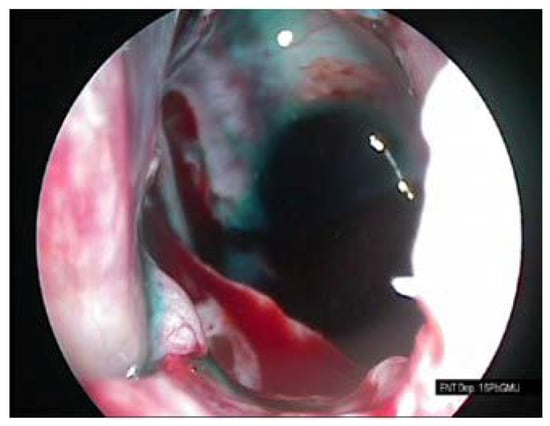

The procedure of the sphenoid sinus volume based on CT scanning followed by 3D reconstruction is illustrated in Figure 1. The corresponding intraoperative measurement procedures are illustrated in Figure 2, Figure 3 and Figure 4.

Figure 4. Sphenoid sinus filled with methylene blue solution.